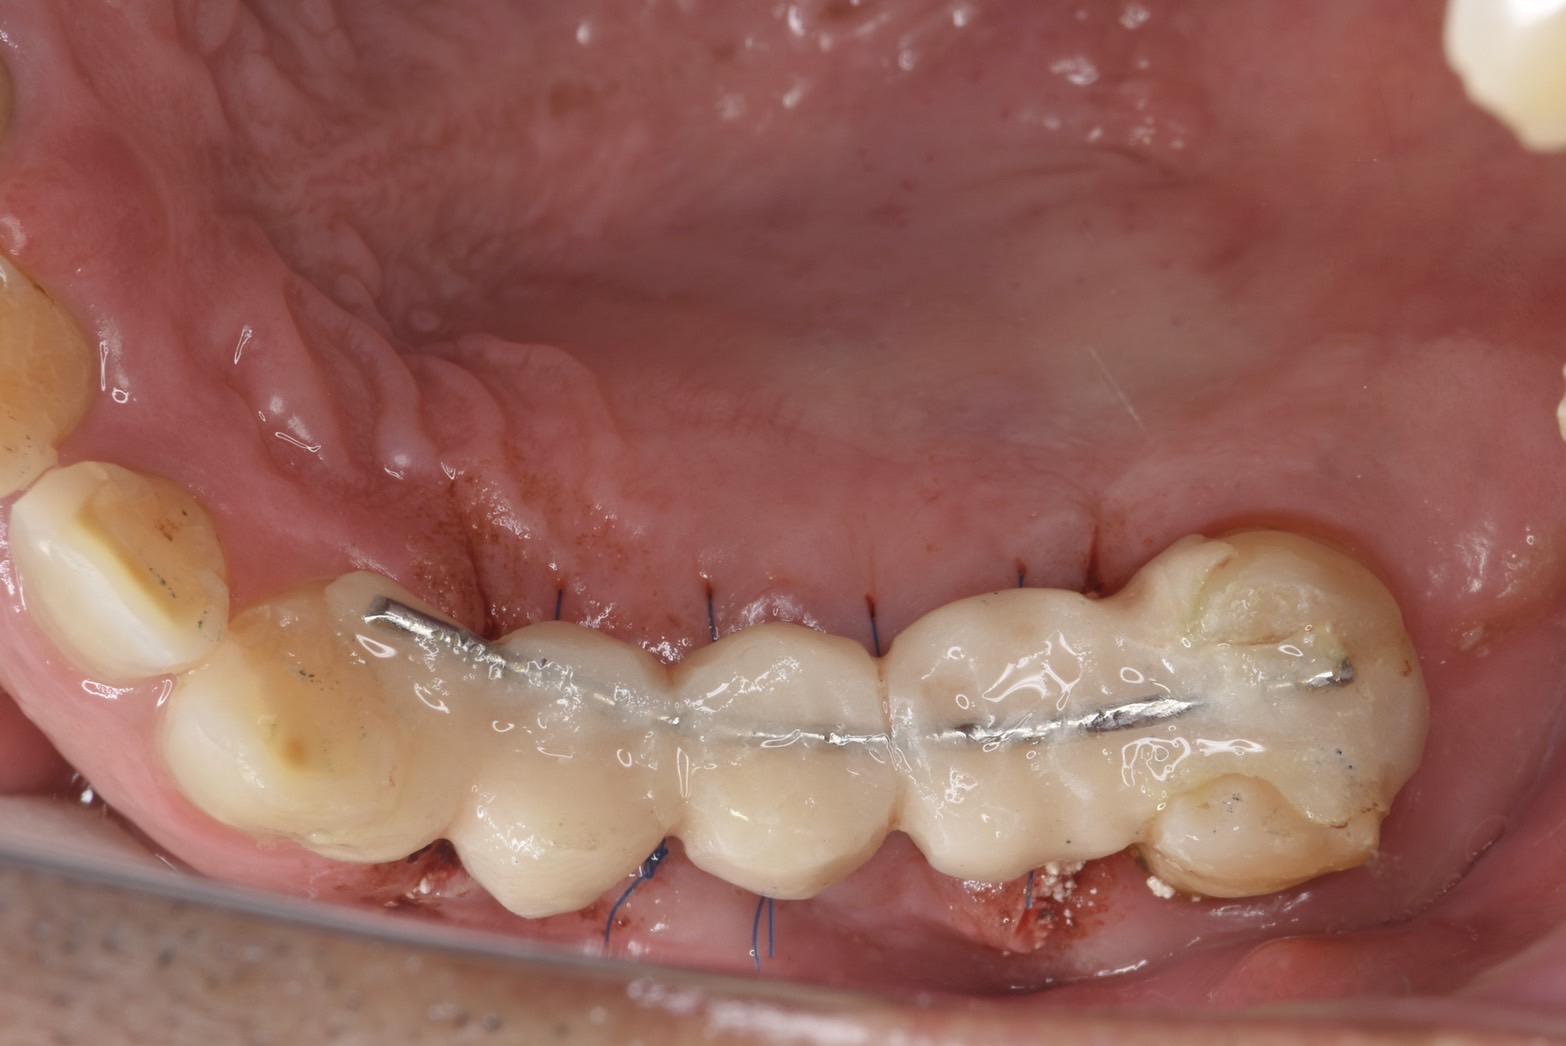

昨年暮れに右上4.6番にデンサーバーのみでのソケットリフトした方の最終セット

今回装着したサイズは直径6ミリと7ミリサイズ 表面積は179と216mm2 単独植立可能な径4.0ミリ長さ10ミリの152m2より断然表面積が大きく、ブラキッサー、クレンチング(歯軋り、食いしばりの方)による、インプラントネック部にかかる負担軽減にはsuperwideは必須です 私もアバットメント、スクリューの破折の経験がありますから